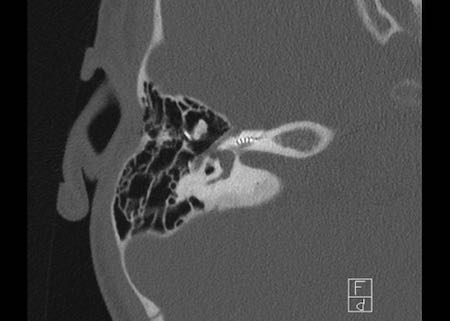

Bên trái là hình ảnh của một bé gái 2 tuổi.

Các hình ảnh từ kết quả chụp CT được thực hiện trước khi cấy ốc tai điện tử.

Quan sát thấy dị dạng nhẹ ở đỉnh ốc tai – không có sự phân tách giữa vòng thứ hai và vòng thứ ba, và trụ ốc tai xương vắng mặt.

Cống tiền đình bình thường.